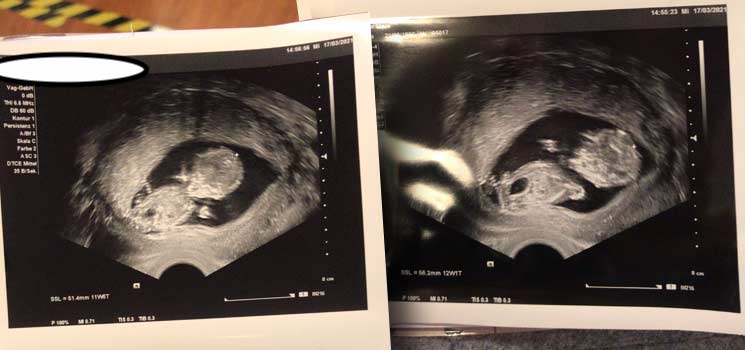

Der erste große Ultraschall stand an! - Tagebücher aus der Schwangerschaft von Jana aus Hamburg